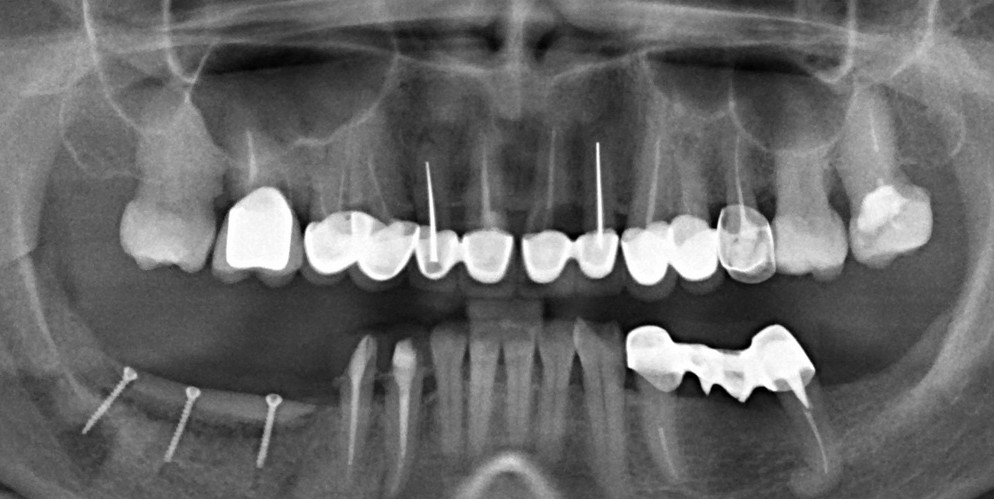

Через год после травмы, девушка обратилась в нашу клинику для восстановления отсутствующего зуба. К тому моменту у нее уже был временный съемный протез, изготовленный в вышеозначенном стоматологическом кабинете, ну и, вот какая клиническая картина:

Хочу спросить вас, уважаемые друзья, можно ли в таком состоянии и при таких объемах альвеолярного гребня поставить имплантат в область отсутствующего зуба? Безусловно, можно. Для этого нужно просто взять имплантат потоньше и поставить его подальше, в сторону неба — и он нормально интегрируется.

На фотографиях хорошо видны оставшиеся после удаления объемы костной ткани. Давайте рассмотрим плюсы и минусы текущей клинической ситуации, применительно к нашему плану:

Фактически, альвеолярный гребень атрофировался по толщине примерно наполовину — это минус.

Зато с высотой все в порядке — это плюс